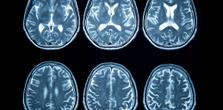

The study revealed a significant association between aerobic fitness levels and myelin content in the brain. Participants with lower maximal oxygen consumption (VO₂ max) exhibited reduced myelination, as indicated by lower myelin water fraction (MWF) values—reflected by more green and blue regions on their brain scans. Conversely, those with higher VO₂ max showed increased myelination, depicted by more red and orange areas on the scans. This gradient suggests that individuals with greater aerobic fitness have better myelin integrity throughout various brain regions.

This relationship was particularly pronounced among the middle-aged (40–59 years) and older adults (60–79 years and 80–94 years). In these age groups, higher aerobic fitness levels corresponded with markedly higher MWF values compared to their less fit counterparts. This finding implies that aerobic fitness may offer protective effects against age-related demyelination, potentially mitigating the decline in myelin integrity that typically accompanies aging.

The data support the notion that physical fitness not only benefits cardiovascular and metabolic health but also plays a crucial role in maintaining neural structure. By enhancing or preserving myelination, higher aerobic fitness could contribute to more efficient neural communication and better cognitive function in older adults.